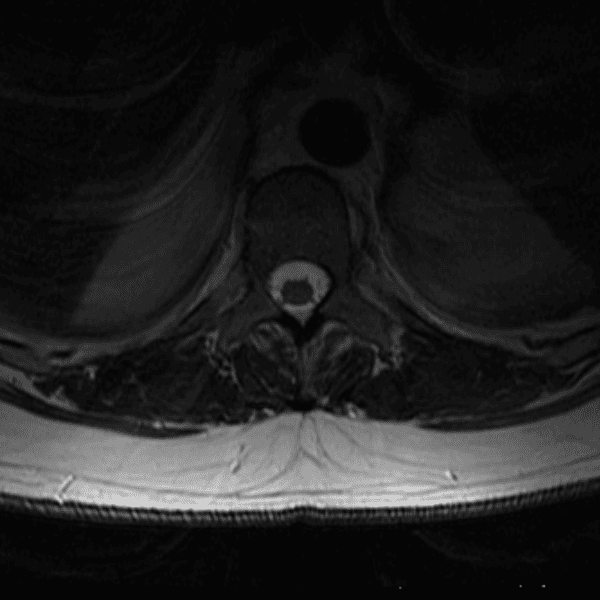

Simulates call by including subtle or difficult cases and some normals.

35 cases